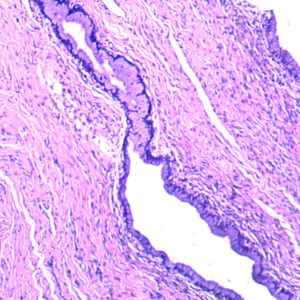

The Pathology teaching slides we offer are professionally hand-mounted, accurately stained, and individually labeled. Our microscope pathology slides are great for medical students, It has an excellent introduction to human disease in microscopy. The Pathology teaching slides are cover-slipped and preserved in cedarwood oil. All slides are carefully labeled for easy reference and are arranged in a fine plastic box with a separator. This pathology teaching slide set includes 14 systems of human diseases. It is excellent for educational use and is perfect for all levels of medical student study including home school programs.

What’s included in this 100pcs pathology teaching slides set: